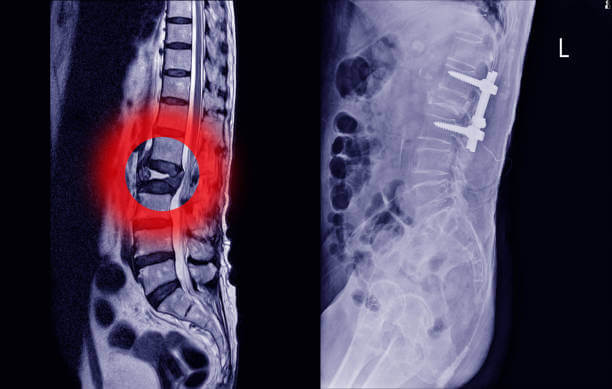

허리디스크(추간판 탈출증)은 척추뼈와 척추뼈 사이의 구조물인 디스크가 탈출된 상태입니다. 일반적으로 허리디스크라고 부르지만 디스크는 구조의 명칭일 뿐, 허리디스크에 해당하는 정확한 질환명은 '허리추간판 탈출증'입니다.

디스크 또는 추간판은 탄성이 뛰어나 외부로부터의 물리적 충격을 완화하고 단단한 뼈 사이의 직접적인 충돌을 방지합니다. 외부의 큰 충격이나 잘못된 자세로 인해 이 디스크가 돌출되면 염증을 일으키고 신경을 압박해 허리 통증, 방사선 통증 등의 통증을 유발합니다.

디스크 속 수핵이 파열되거나 튀어나와 수핵이 섬유륜 쪽으로 밀려나 추간판이 튀어나오게 됩니다. 허리디스크 초기에는 허리통증보다 통증의 강도가 더 심하고 다른 증상들도 함께 나타납니다. 일상생활 중 허리 통증은 불편함을 증가시킬 수 있으며, 허리 통증은 많지 않으나 골반, 다리, 발가락 등의 저림이나 통증이 나타날 수 있습니다.

말기 단계

추간판 탈출증 상태에서는 수핵의 일부가 섬유륜을 찢고 추간판 조직과 분리됩니다. 심한 요통과 일상생활이 불가능할 정도로 움직임이 심하게 제한됩니다. 요통이 심해지면 하반신 마비로 이어질 수 있어 빠른 치료를 해야합니다.